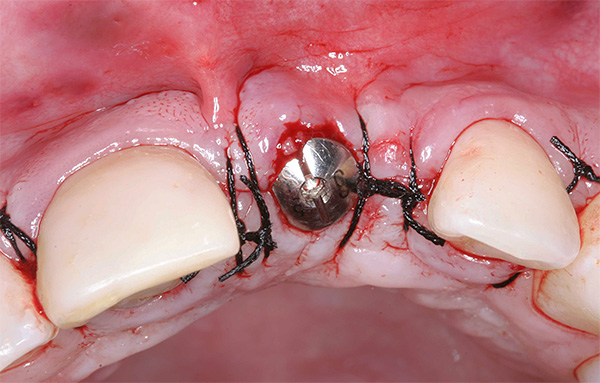

A foto abaixo mostra um exemplo correspondente (a inflamação começou 10 anos após a instalação do implante):